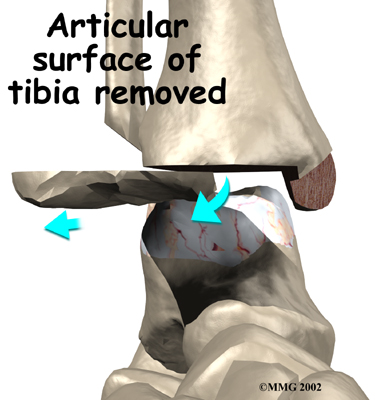

Several different operations have been developed to perform an ankle fusion. The basic procedure in each operation remains the same, however. The most common way that an ankle fusion is done is by making an incision through the skin to open the joint. Once the joint is opened, the surgeon uses a surgical saw to remove the articular cartilage surfaces of the ankle joint. Once the articular cartilage is removed on both sides of the joint, the body will try to heal the two surfaces together just as if it were fractured or broken.

Removing the articular surface of the tibia